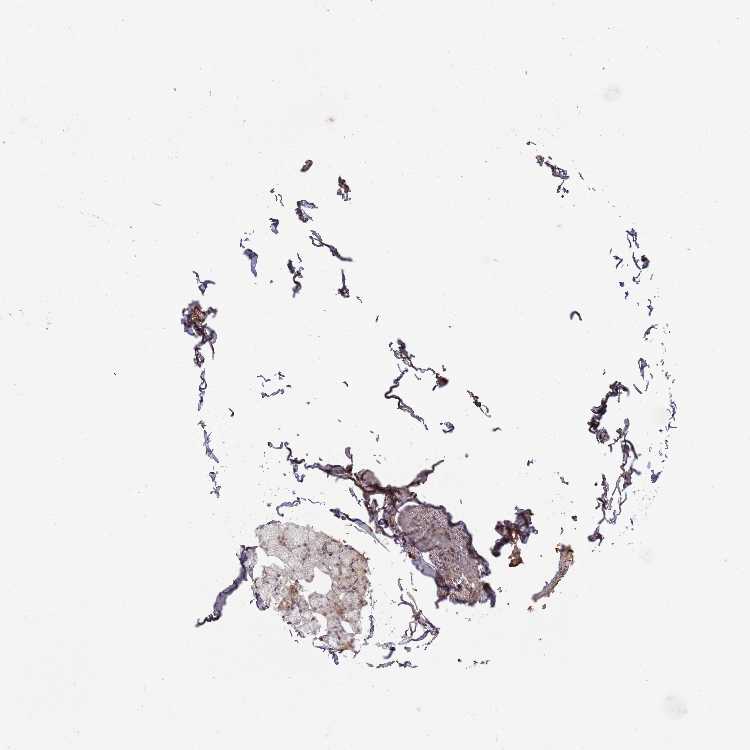

SOFT TISSUE 1 - Antibody stainingi

Antibody staining in the annotated cell types in the current human tissue is reported as not detected, low, medium, or high, based on conventional immunohistochemistry profiling in selected tissues. This score is based on the combination of the staining intensity and fraction of stained cells.

Each image is clickable and will lead to virtual microscopy that enables deeper exploration of all samples and also displays staining intensity scores, fraction scores and subcellular localization as well as patient and tissue information for each sample.

Antibody HPA047126Antibody HPA054655

Chondrocytes MediumNot detected

Fibroblasts MediumNot detected

Peripheral nerve -Not detected